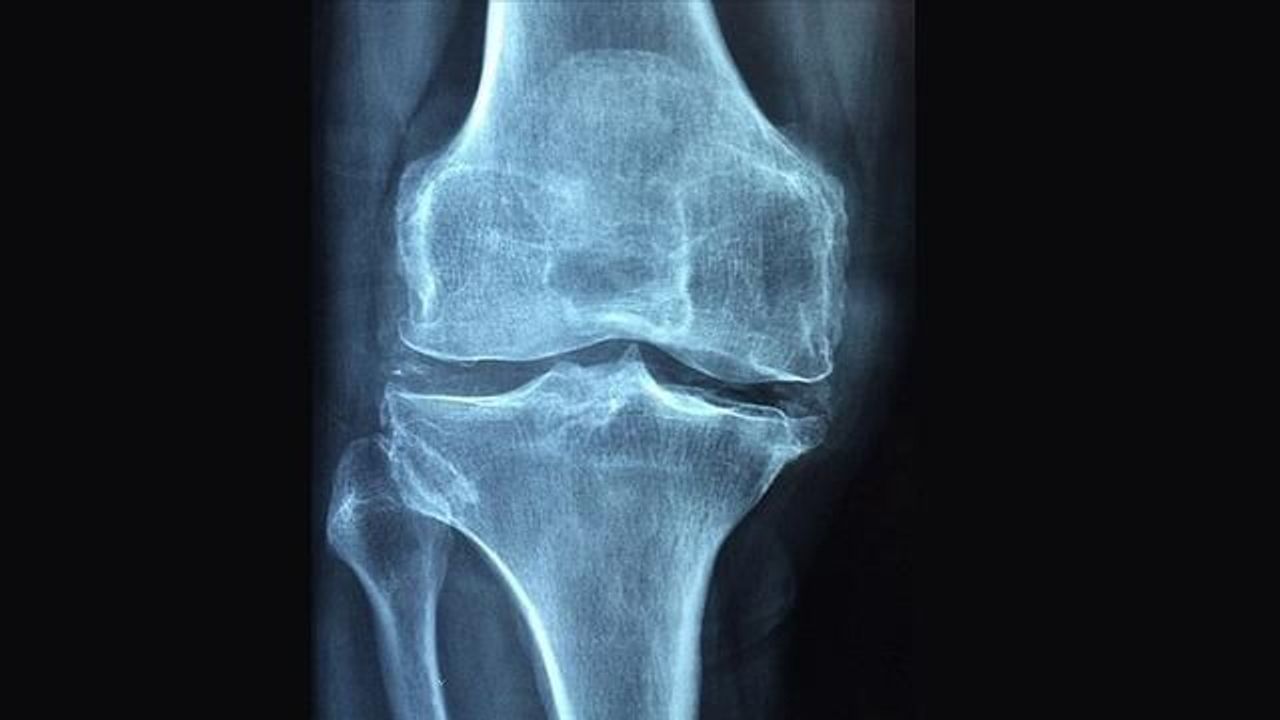

Dr. Tutal, osteoporozun en çok kalça, bel ve bilek kemiklerinde kırıklara yol açtığını ve hem kadınları hem de erkekleri etkileyen bir hastalık olduğunu söyledi. İleri dönemlerde sırt ve bel ağrısı, boy kısalması ile duruş bozukluklarının görülebileceğini kaydetti.

Kemik yapım ve yıkımının dengede olması gerektiğine dikkat çeken uzman, 30 yaşından sonra kemik yıkımının arttığını ve bu nedenle maksimum kemik kitlesinin önem taşıdığını belirtti. Ayrıca, kortizonlu ilaç kullanımı, hareketsiz yaşam, sigara ve alkol tüketimi gibi faktörlerin kemik erimesi riskini artırdığını vurguladı.